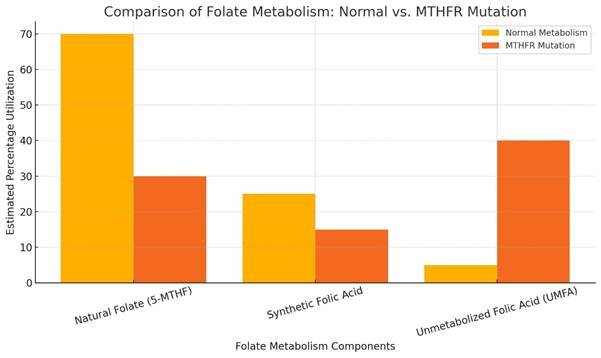

- Valproate has been shown to inhibit enzymes in the folate cycle, such as methylenetetrahydrofolate reductase (MTHFR) and dihydrofolate reductase (DHFR). This inhibition can reduce the availability of 5-methyltetrahydrofolate (5-MTHF), the bioactive form of folate required for homocysteine remethylating and DNA methylation.

- Numerous public health conclusions on neural tube defect prevention have been based on a mixed body of research that often fails to distinguish between naturally occurring folate and synthetic folic acid. This conflation is evident in studies and policy guidance, as noted by Lucock (2000), Smith et al. (2008), and Pfeiffer et al. (2015), despite the substantial metabolic differences between these compounds – especially in genetically vulnerable populations.

“Many studies and policies do not distinguish clearly between folate and folic acid, despite differences in bioavailability and metabolism” – Lucock (2000) – British Journal of Biomedical Science

The CDC’s early evaluation of folic acid fortification outcomes in 1998 relied on dietary intake surveys that also did not distinguish between natural folate and synthetic folic acid. While these findings were used to support the benefits of fortification, they were based on estimated “folate equivalents,” conflating naturally occurring and fortified sources (CDC, 1998). This conflation undermines the precision of conclusions drawn about the specific effects of synthetic folic acid, especially in populations with genetic vulnerabilities to UMFA accumulation. Through artificially boosting folic acid intake, industry-created data distortions allowed them to claim that NTD prevalence was declining, even when valproate-exposed pregnancies showed persistently high rates of defects.

Firstly, the assertion that folic acid is the optimal intervention ignores the growing body of evidence that natural methylated folates (e.g. L-5-methyltetrahydrofolate) may offer superior bioavailability, especially for individuals with impaired folate metabolism due to MTHFR or MTRR polymorphisms (Scaglione and Panzavolta, 2014). Many studies have proven that synthetic folic acid requires enzymatic activation that may be significantly compromised in populations with reduced MTHFR activity – raising questions about both efficacy and safety in these individuals (Bailey and Ayling, 2009).

Despite issuing categorical assurances that individuals with MTHFR gene variants “can process all types of folates, including folic acid,” the CDC fails to substantiate these claims with any robust scientific evidence (CDC, 2023). The CDC’s public guidance regarding MTHFR gene variants and folic acid supplementation references a narrow selection of sources, notably a general mechanistic review by Crider et al. (2012) and the OMIM (Online Mendelian Inheritance in Man) database. However, these sources do not provide direct empirical evidence supporting the safety of synthetic folic acid in individuals with impaired folate metabolism – particularly those homozygous for the C677T MTHFR variant, whose ability to convert folic acid to biologically active forms are significantly reduced (Crider et al., 2012; OMIM, 2024).

The Crider et al. review focuses primarily on the role of folate in DNA methylation and epigenetic regulation, with extensive discussion of biochemical pathways and theoretical mechanisms. While it affirms folate’s importance in early development, it does not distinguish between natural folate, synthetic folic acid, or L-methylfolate, nor does it assess population-level responses in MTHFR-compromised individuals (Crider et al., 2012). Moreover, it offers no clinical outcome data or longitudinal safety findings for this subgroup.

This failure to provide adequate evidence constitutes a breach of scientific transparency and undermines the legitimacy of public health recommendations affecting genetically vulnerable groups. In contrast to this omission, independent research has consistently demonstrated that MTHFR variants can impair folic acid metabolism, potentially resulting in functional folate deficiency, neurodevelopmental impact, and increased risk of adverse outcomes when synthetic folic acid is consumed in excess or without adequate conversion (Lucock et al., 2014; Smith et al., 2008).

Most notably, the NHS provides no public guidance regarding MTHFR gene polymorphisms, despite these being well-established genetic determinants of folate metabolism. Up to 14% of the UK population may carry homozygous (two copies) MTHFR C677T variants (Hazra et al., 2009), which significantly impair enzymatic conversion of synthetic folic acid into its bioactive form. The absence of any reference to these metabolic impairments constitutes a critical oversight, particularly in the context of population-wide fortification and high-dose prescription protocols.